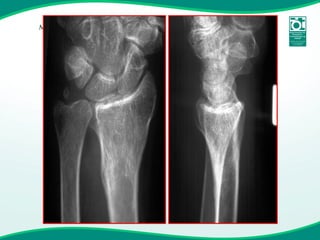

Fratura instável & Osteoporose

Fratura Instável